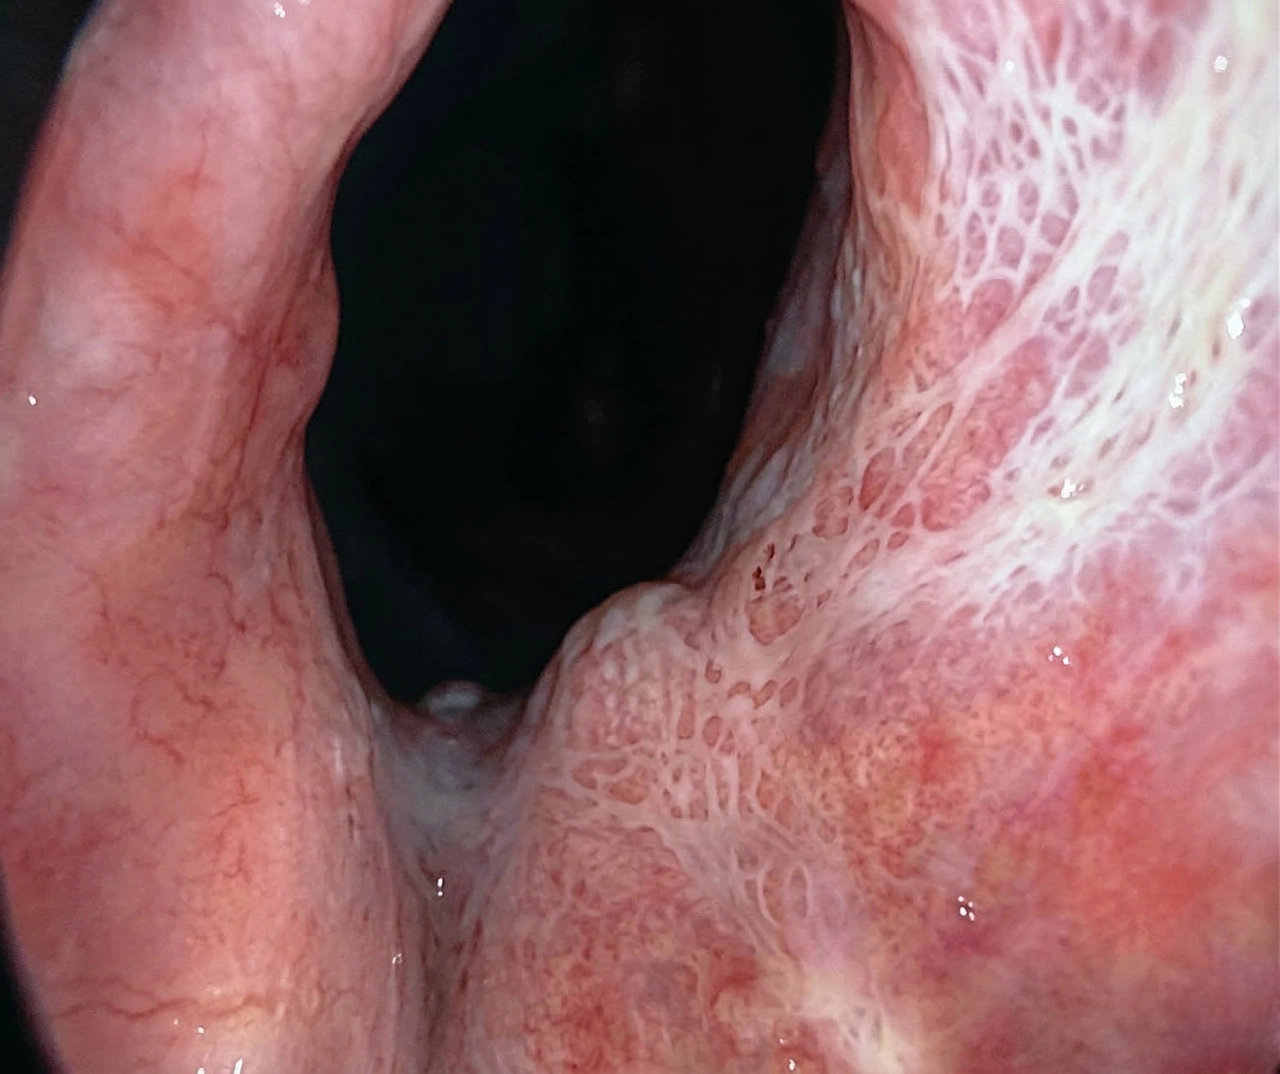

유로리프트 시술 전후

유로리프트 시술을 하게 되면 좁아진 요도관이 넓어져 소변의 문제가 해결됩니다.

전립선의 문제도 같이 해결이 됩니다.